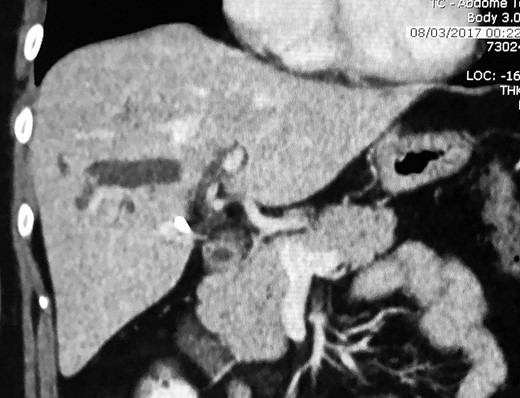

Physical examination revealed right hypochondrial tenderness but was otherwise unremarkable. Laboratory investigation revealed normal bilirubin, aspartate aminotransferase, and alanine aminotransferase, and gamma-glutamyl transpeptidase of 550 U/L (normal up to 50 U/L) and alkaline phosphatase of 350 U/L (normal up to 120 U/L). Abdominal ultrasound revealed a dilated intrahepatic duct with stones, but no extrahepatic stone was observed. Abdominal computed tomography showed stones within a dilated intrahepatic bile duct of segment 6 and a small radiopaque image with metallic density (Fig. 1). Magnetic resonance cholangiopancreatography (MRCP) revealed a dilated intrahepatic bile duct of segment 6 filled with stones. A single filling defect in the distal common bile duct was also observed (Fig. 2). The case was discussed at a hepatobiliary meeting. Due to the difficult position of the stones (segment 6), endoscopic retrograde cholangiopancreatography was not possible and liver resection was indicated. The patient underwent surgery after preoperative evaluation.